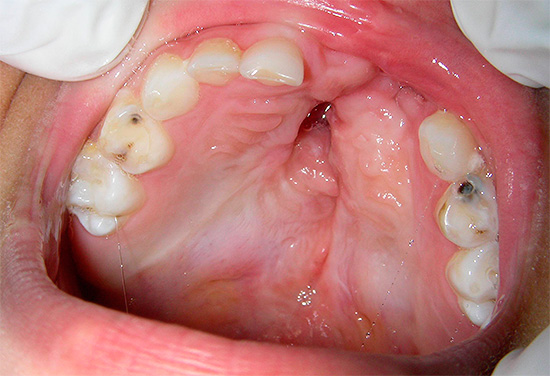

Foto do fluxo na gengiva de uma criança: